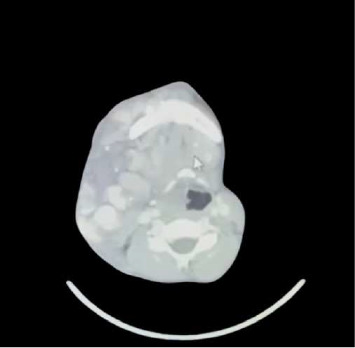

由于气道管理的复杂性和出血风险,头颈部动静脉畸形(AVMs)提出了重大挑战。这个病例报告描述了一个15岁的女性先天性面部AVM引起呼吸困难和阻塞性症状。患者需要对动静脉畸形进行血管栓塞,但许多医院由于预期气道困难和严重出血风险而推迟了手术。我们做了两次清醒纤维插管的尝试,但由于患者不耐受未能成功。随后,开始吸入诱导并进行视频喉镜检查,但由于解剖扭曲而失败。尝试气囊面罩通气后,开始出现严重静脉充血,患者出现大出血和循环衰竭,需要长时间的复苏和插管。最终,通过吸痰辅助喉镜和视频喉镜净化技术,在40分钟后插管成功。她接受了血管栓塞术并转移到ICU,在那里她保持了9天的机械通气。气管切开术后,患者逐渐脱离呼吸机,随后出院。该病例强调了细致的计划、全面的气道评估、备用策略和多学科支持的必要性,提示视频喉镜检查是高危出血病例的一个有价值的选择。

Arteriovenous malformations (AVMs) in the head and neck present significant challenges due to airway management complexities and hemorrhage risks. This case report describes a 15-year-old female with a congenital facial AVM causing dyspnea and obstructive symptoms. The patient required angioembolization of the AVM, but many hospitals deferred the procedure due to the anticipated difficult airway and severe bleeding risks. We did two attempts of awake fiberoptic intubation but could not succeed due to patient intolerance. Subsequently, inhalational induction started and video laryngoscopy performed but also failed due to anatomical distortion. With attempts to bag mask ventilate, severe venous engorgement started and patient experienced massive hemorrhage and circulatory collapse, necessitating prolonged resuscitation and intubation efforts. Eventually, intubation was successful after 40 min using suction assisted laryngoscopy and decontamination (SALAD) technique by video laryngoscope. She underwent angioembolization and shifted to the ICU where she remained on mechanical ventilation for 9 days. After tracheostomy was performed, she was gradually weaned off from ventilator and was later discharged. This case highlights the need for meticulous planning, comprehensive airway evaluation, backup strategies, and multidisciplinary support, suggesting video laryngoscopy as a valuable alternative in high-bleeding-risk cases.